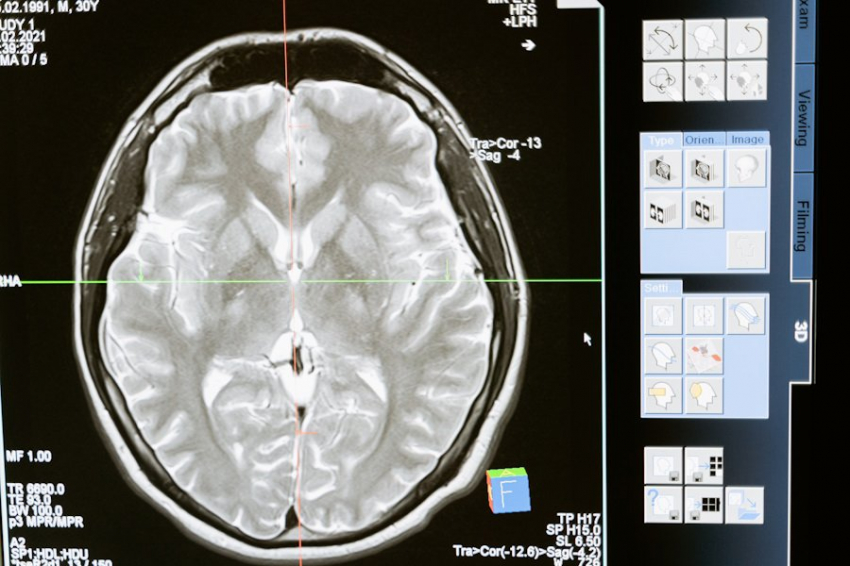

Фото из открытых источников

Пресенильный психоз — это термин, который врачи используют для описания деменции, когда не удается точно определить причину заболевания. Деменция может возникнуть по разным причинам: травмы головы, сосудистые поражения мозга или болезнь Альцгеймера. Об этом сообщает «Газета.Ru».

Все эти расстройства относятся к категории «органических психических расстройств», что означает наличие повреждений и изменений в тканях головного мозга.